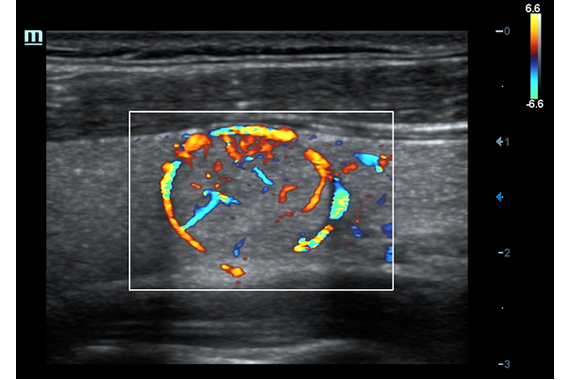

–ú–Ω–æ–≥–æ—Ñ—É–Ω–∫—Ü–∏–æ–Ω–∞–ª—å–Ω–∞—è —Å–∏—Å—Ç–µ–º–∞ DC-60 Exp —Å X-Insight –ø—Ä–µ–¥—Å—Ç–∞–≤–ª—è–µ—Ç —Å–æ–±–æ–π –∫–æ–º–ø–ª–µ–∫—Å–Ω–æ–µ —Ä–µ—à–µ–Ω–∏–µ, –∫–æ—Ç–æ—Ä–æ–µ –ø–æ–º–æ–≥–∞–µ—Ç —É–ø—Ä–∞–≤–ª—è—Ç—å –ø–æ–≤—Å–µ–¥–Ω–µ–≤–Ω–æ–π –∫–ª–∏–Ω–∏—á–µ—Å–∫–æ–π –ø—Ä–∞–∫—Ç–∏–∫–æ–π —Å –ª–µ–≥–∫–æ—Å—Ç—å—é –∏ —É–≤–µ—Ä–µ–Ω–Ω–æ—Å—Ç—å—é.

–û—Å–Ω–æ–≤—ã–≤–∞—è—Å—å –Ω–∞ –≥–ª—É–±–æ–∫–æ–º –ø–æ–Ω–∏–º–∞–Ω–∏–∏ –ø–æ—Ç—Ä–µ–±–Ω–æ—Å—Ç–µ–π –∫–ª–∏–µ–Ω—Ç–æ–≤, –∫–æ–º–ø–∞–Ω–∏—è Mindray —Ä–∞–∑—Ä–∞–±–æ—Ç–∞–ª–∞ —Å–∏—Å—Ç–µ–º—É DC-60 Exp —Å X-Insight, —á—Ç–æ–±—ã –æ–±–µ—Å–ø–µ—á–∏—Ç—å –≤—ã—Å–æ–∫—É—é –ø—Ä–æ–∏–∑–≤–æ–¥–∏—Ç–µ–ª—å–Ω–æ—Å—Ç—å –∏ —Ç–æ—á–Ω–æ—Å—Ç—å –≤–∏–∑—É–∞–ª–∏–∑–∞—Ü–∏–∏ –≤–∫—É–ø–µ —Å –Ω–∞–≥–ª—è–¥–Ω–æ—Å—Ç—å—é, –∏—Å–∫–ª—é—á–∏—Ç–µ–ª—å–Ω–æ–π –∏–Ω—Ç–µ–ª–ª–µ–∫—Ç—É–∞–ª—å–Ω–æ—Å—Ç—å—é –∏ –æ–≥—Ä–æ–º–Ω—ã–º –æ–ø—ã—Ç–æ–º.